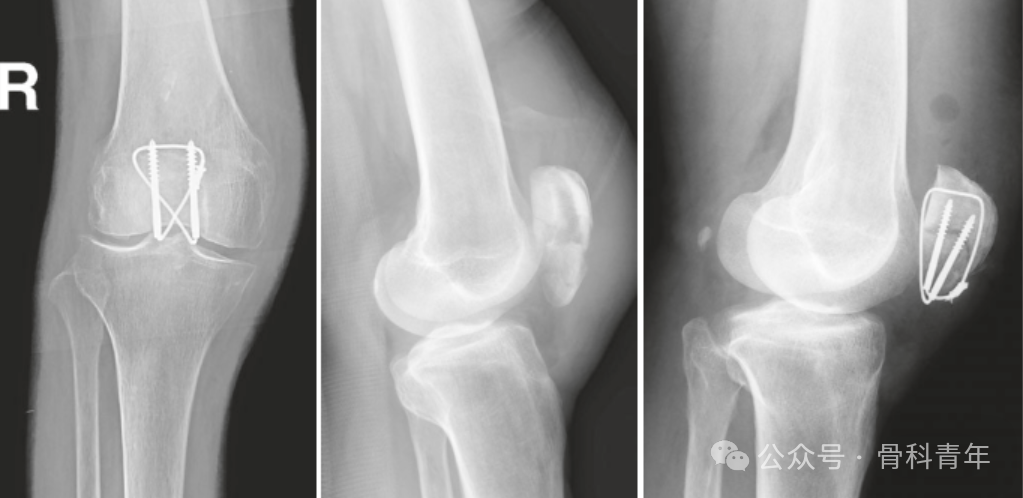

复位钳或巾钳临时维持复位后,经髌骨上缘或下缘,平行置入2枚2mm克氏针,克氏针置入点需距离髌骨前方皮质5mm,在冠状面与矢状面上于髌骨关节面平行。关于克氏针在冠状面上的位置,有学者认为克氏针应紧贴关节面已达到最好的张力带效果,也有学者认为克氏针应位于矢状面中后1/3处。不论哪种方式,克氏针均不可过于靠近髌骨前方,否则膝关节屈膝后后方骨折线张口,无法达到张力带目的。

除克氏针张力带外,对髌骨横行简单骨折,更多学者采用空心螺钉先将骨块复位加压,并通过空心钉孔置入钢丝,可以达到有效的张力带效果,并可避免克氏针滑出。